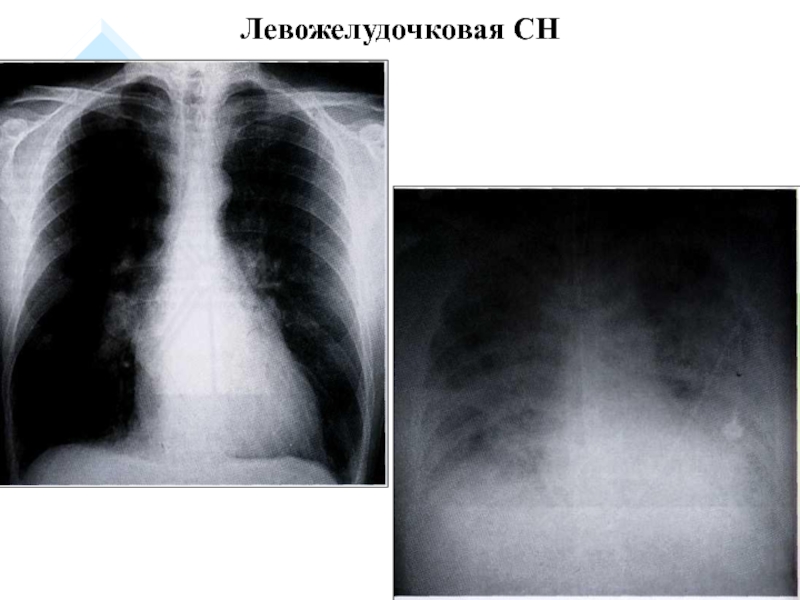

Слайд 14Левожелудочковая СН

Левожелудочковая СН

1. Левожелудочковая СН: ↑ давление

крови в легочных венах, сосудах малого круга, в правом желудочке

(застой) → сердечная астма, отек легких.